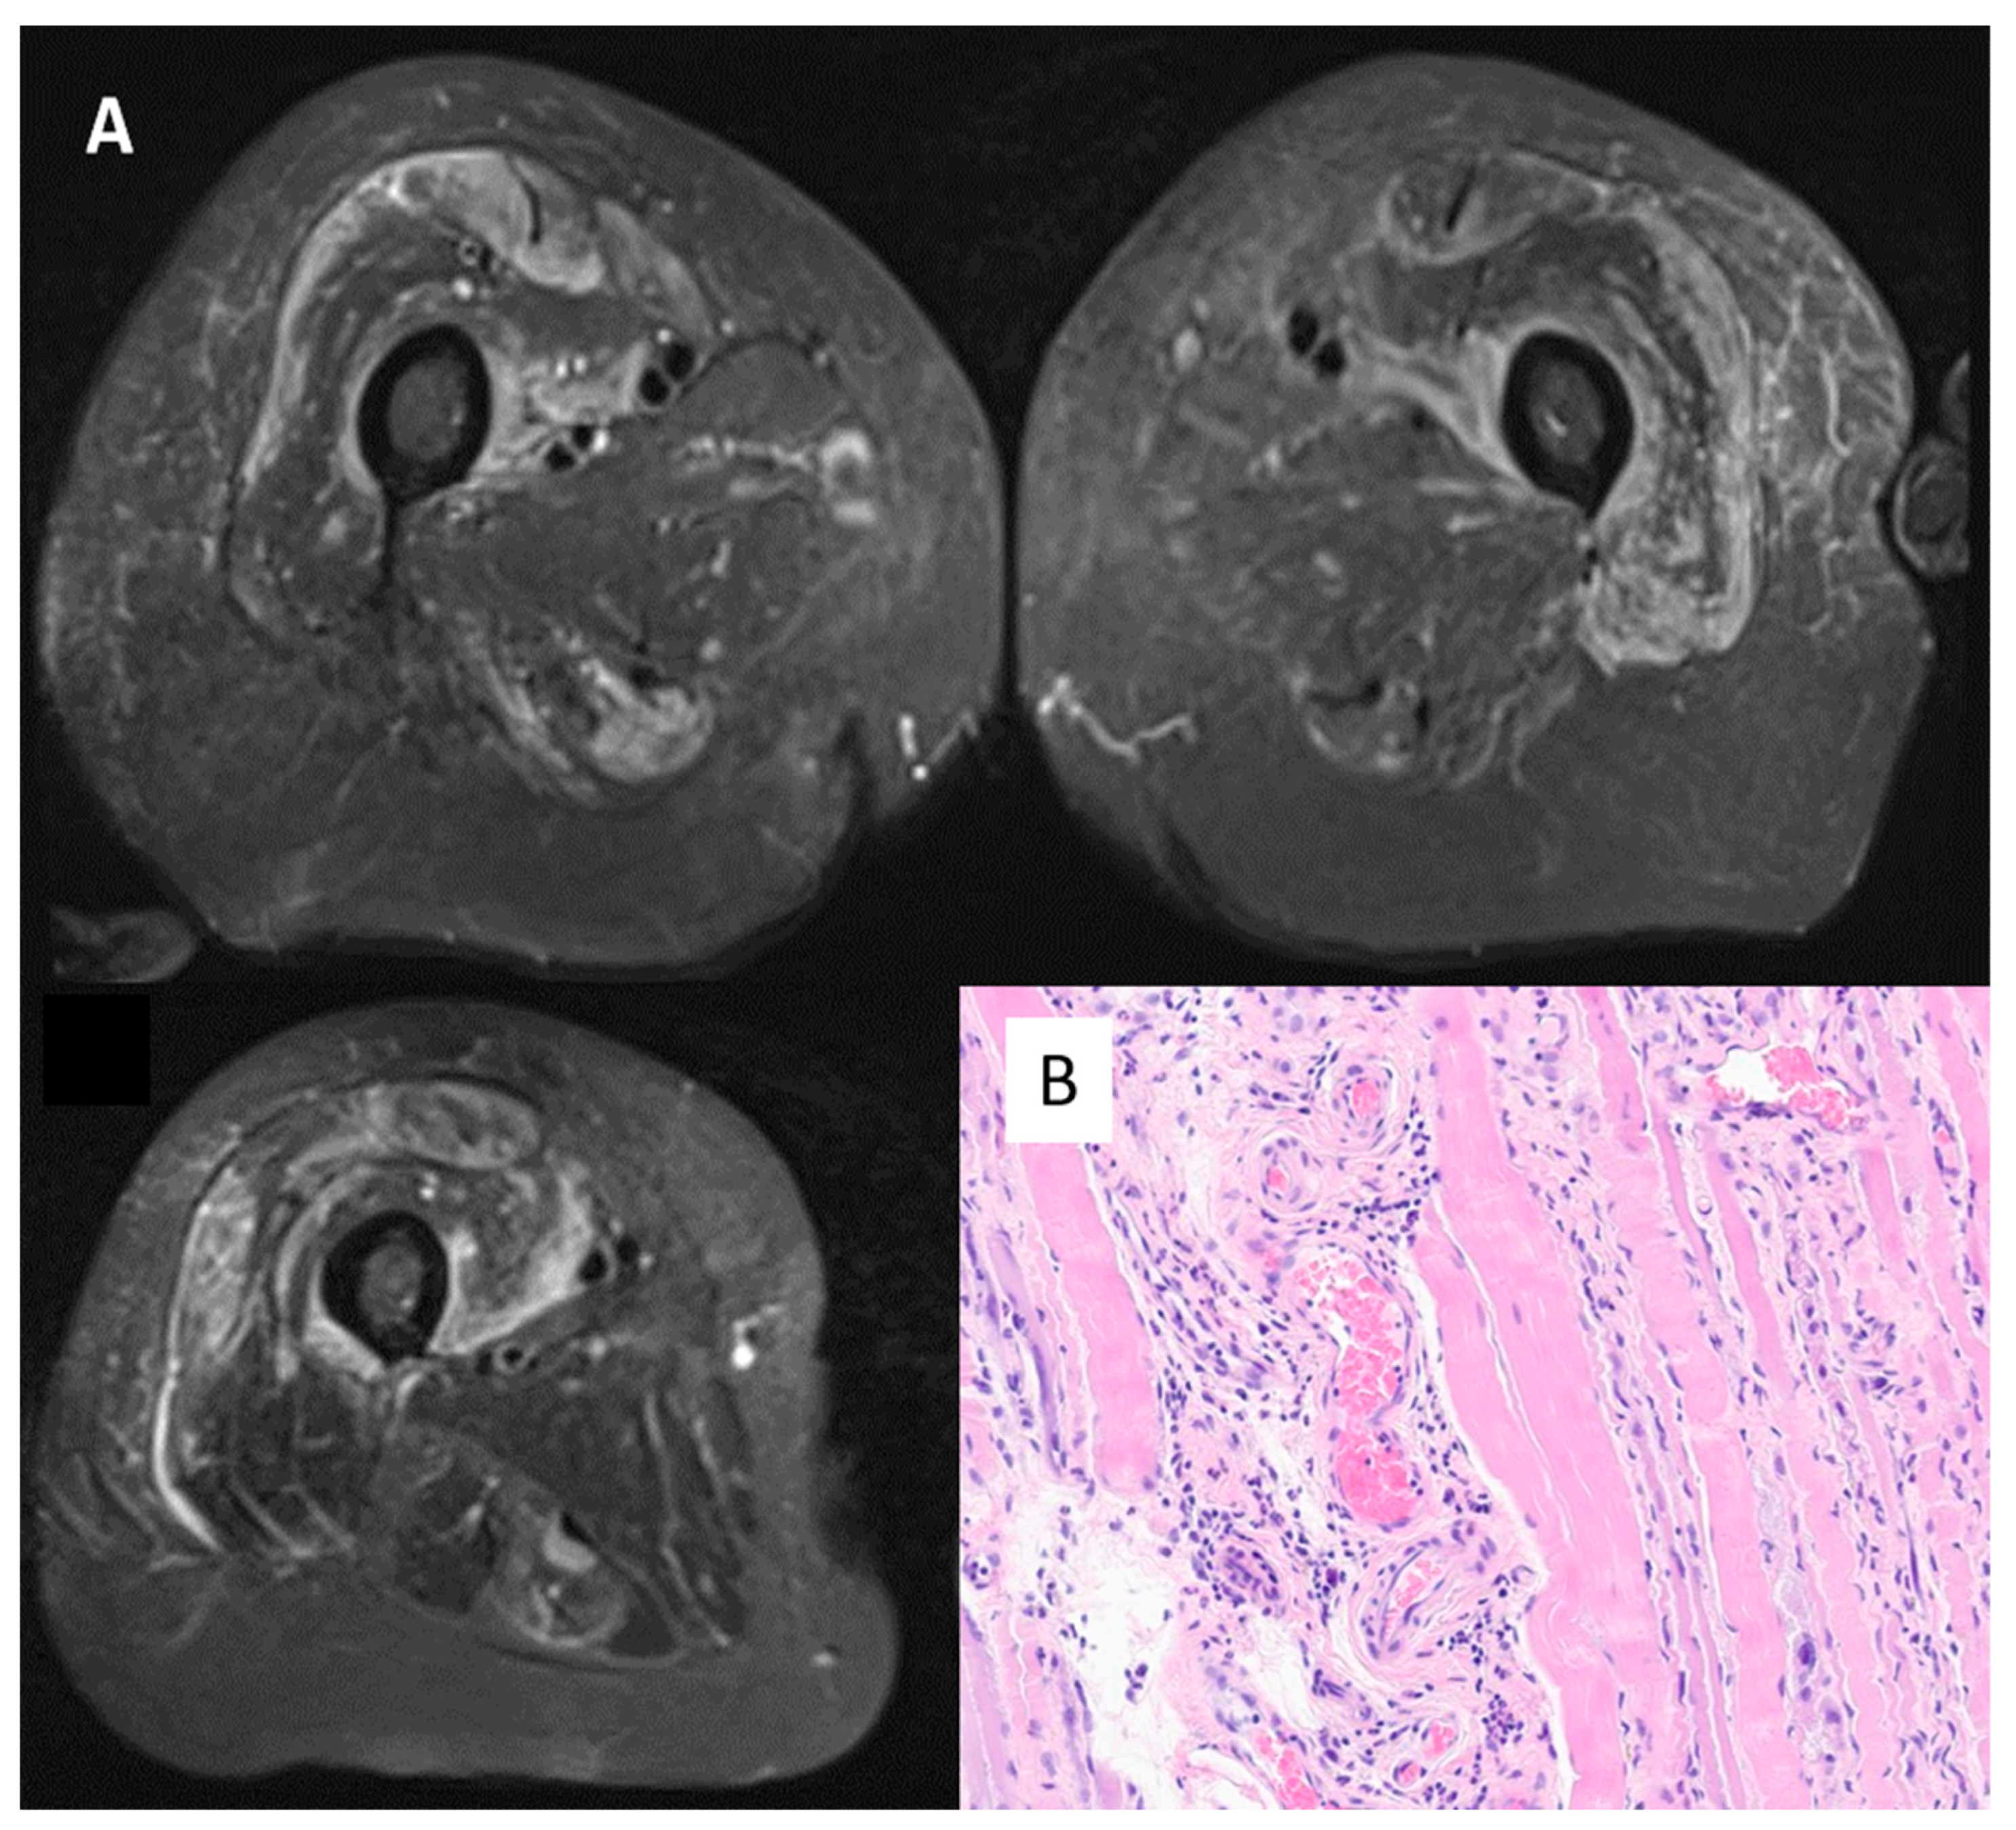

| Case 6 | No | AZD1222/ChAdOx1 | Asthenia, myalgia. CK 7598 U/L, CRP normal, myositic pattern on EMG, muscle oedema on MRI, biopsy positive ANA negative Myoblot + (Pl12 and Scl100) | No | Steroids, then azathioprine and one IV drip of immunoglobulins |

| Bradford | dose 2, February 2021 | ||||

| Female, 76 | (5 weeks) | ||||

| Case 7 | No | BNT162b2 | Asthenia, myalgia. CK 15,212 U/L, CRP 13 mg/L, muscle oedema on MRI, necrosis-related features on biopsy ANA negative, Myoblot negative Anti-HMGCR + | No | Steroids, then two IV drips of immunoglobulins |

| Bradford | dose 3, November 2021 | ||||

| Male, 64 | (5 weeks) | ||||